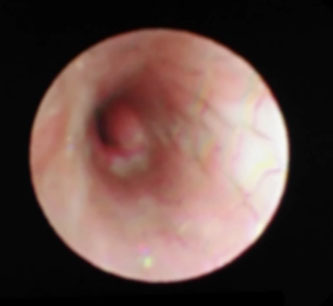

支架植入术后左主支气管管腔通畅

半个月后气管镜复查,小宝宝的支架内未见肉芽组织增生,管腔很通畅,现已拔掉气管插管。